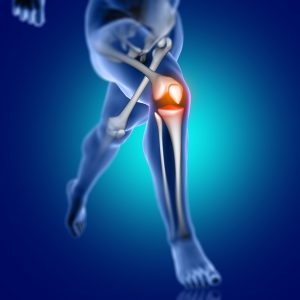

Most of the time we focus on the bigger muscle groups, which eventually take over and cause all sorts of problems with the rest of the kinetic chain. Start with the smaller, internal stabilizers; get those muscle on board first and then look to the outer. What ever sport you are involved in, these programs will help link the kinetic chain together properly, allow you to perform at you optimal without injury.